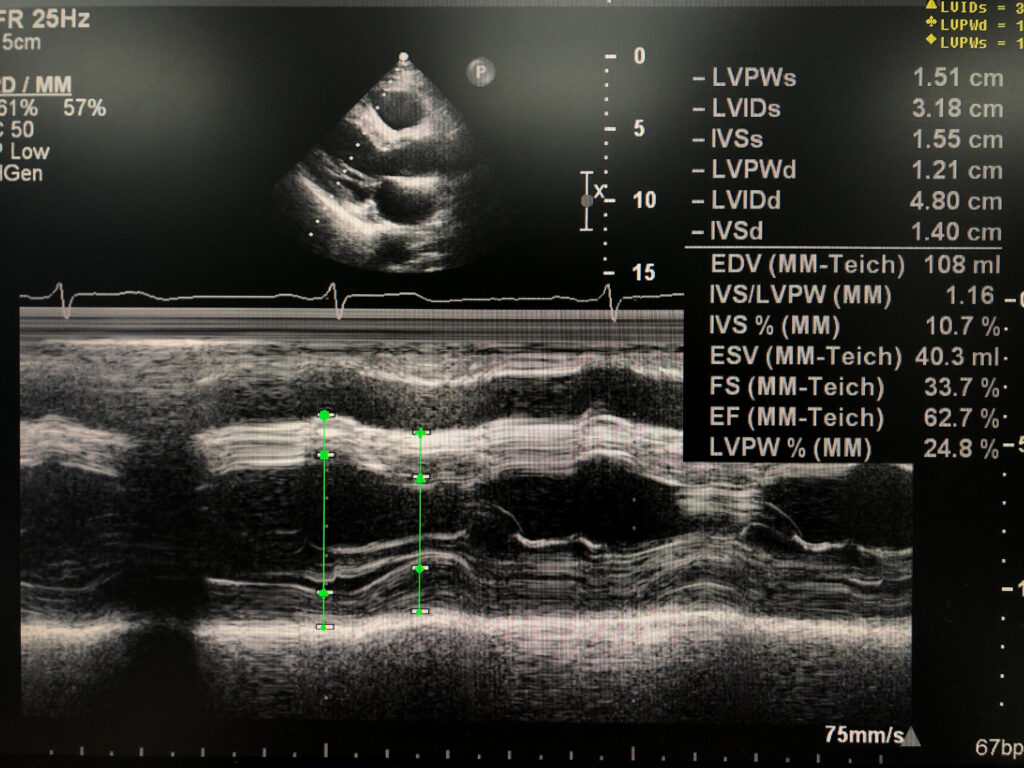

One-Dimensional Echocardiography: Still Needed or Already Outdated?

There is a widespread lack of knowledge about one-dimensional echocardiography (M-mode) by the current generation of echocardiographers. Has two-dimensional echocardiography (B-mode) and Doppler made M-mode outdated? M-mode provides information that cannot be obtained by using B-mode or even Doppler—be it spectral, color, or tissue Doppler—for two reasons: